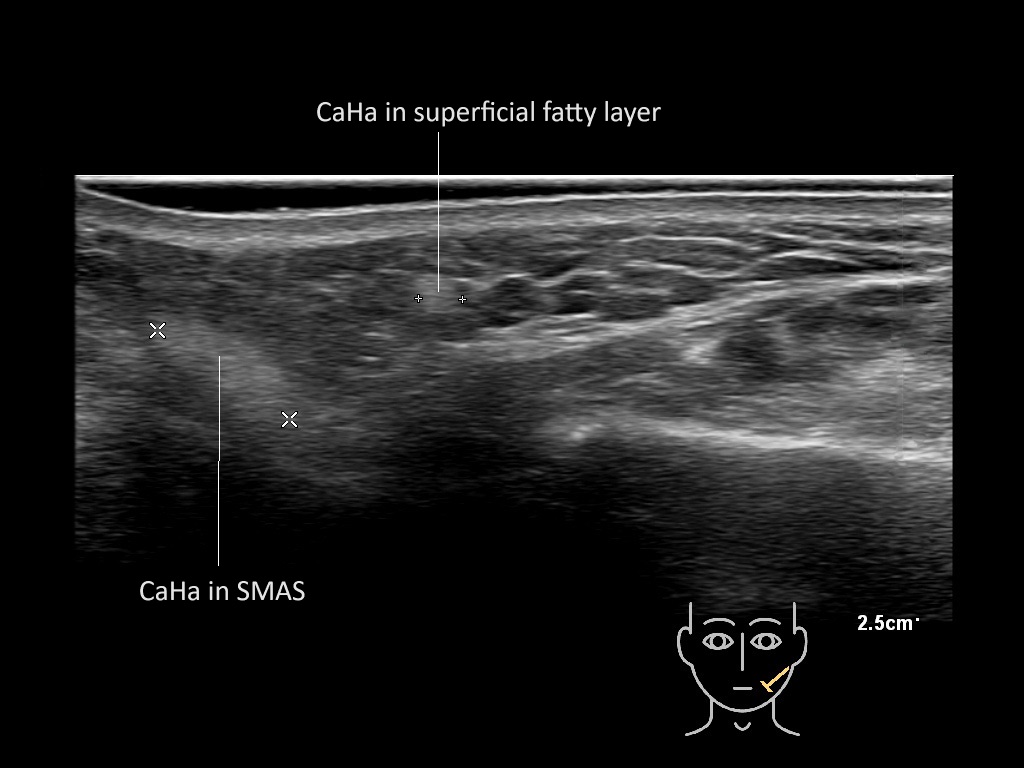

Filler deposits may end up unintentionally in the SMAS or fascial layers of the skin. Very often this will not lead to adverse events, however, adverse events ( nodules, migration / redistribution impaired muscle movement and smiling and malar edema) are are often related to filler ending up in the SMAS or fascia.

Hover over an image to view the secondary image or click on the image title for more information.